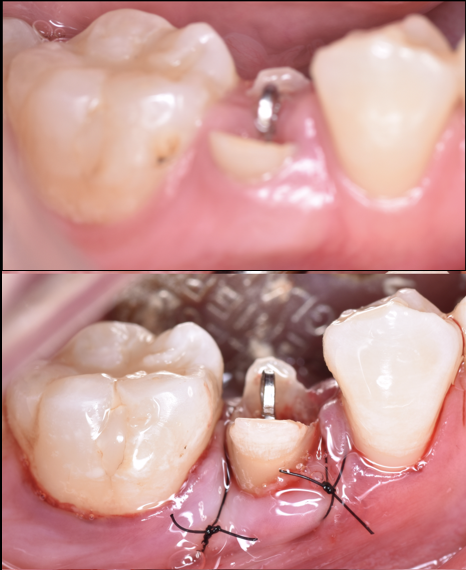

折れた歯を残す「エクストルージョン」という選択...